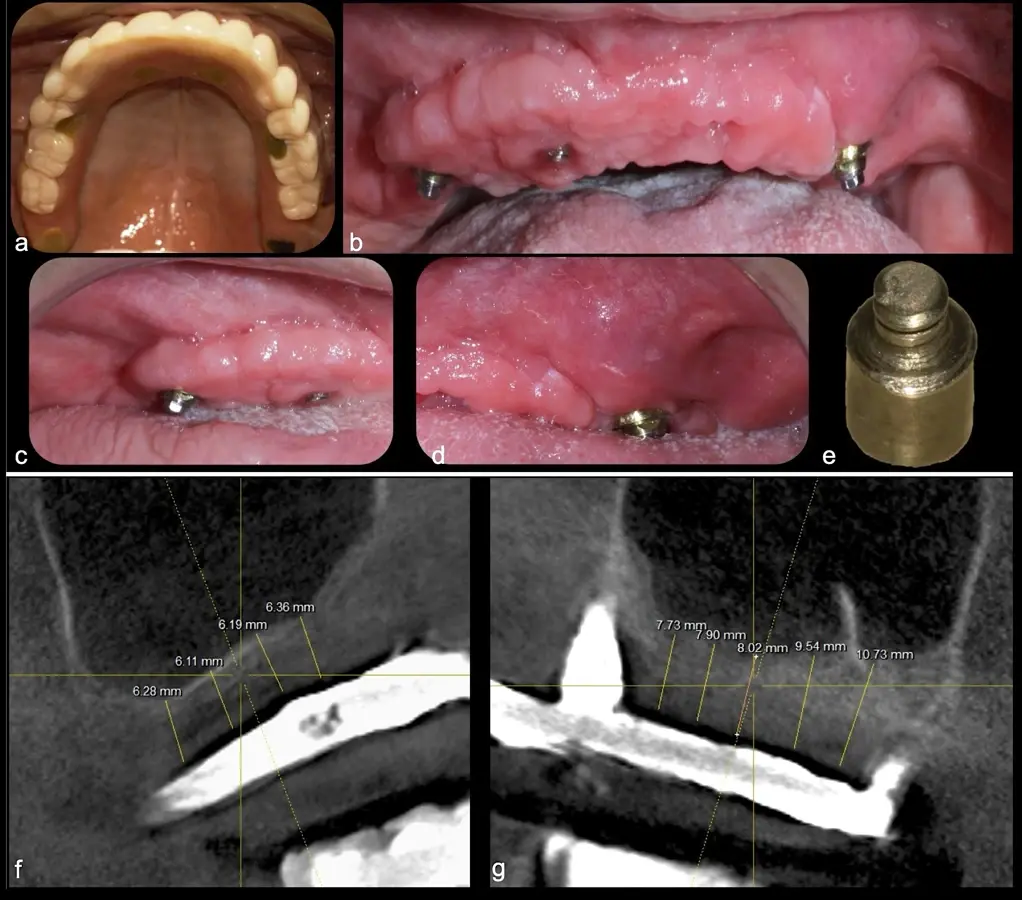

El levantamiento de piso de seno maxilar es una técnica quirúrgica aceptada previa o simultáneamente a la colocación de implantes dentales. La mayor evidencia científica refiere que si se tiene entre 0 -7 mm de altura ósea se debe realizar la elevación sinusal junto con injertos óseos; y a partir de los 8 mm, se hace más predecible la colocación simultánea de implantes dentales.1-3

Aunque esta técnica es predecible, la perforación de la membrana sinusal es la complicación intraoperatoria más común, con una prevalencia de hasta el 58.3%.4 Existen también otras complicaciones reportadas, como hemorragias asociadas a la lesión de la anastomosis arterial en el área de la pared lateral del seno maxilar.5-8

El tipo de inserto a ser utilizado dependerá del espesor de la pared ósea. Si la pared es menor a 0.5 mm, es mejor utilizar insertos de desgaste para prevenir la ruptura de la membrana de Schneider; si el espesor es mayor a 0.5 mm, se puede utilizar insertos de corte de espesor medio (Figura 3).

El clínico puede retirar la tabla ósea o introducirla como “tienda de campaña” dentro del seno maxilar. En cualquiera de las alternativas, es importante evaluar la presencia de tabiques óseos y de la arteria postero alveolar superior.